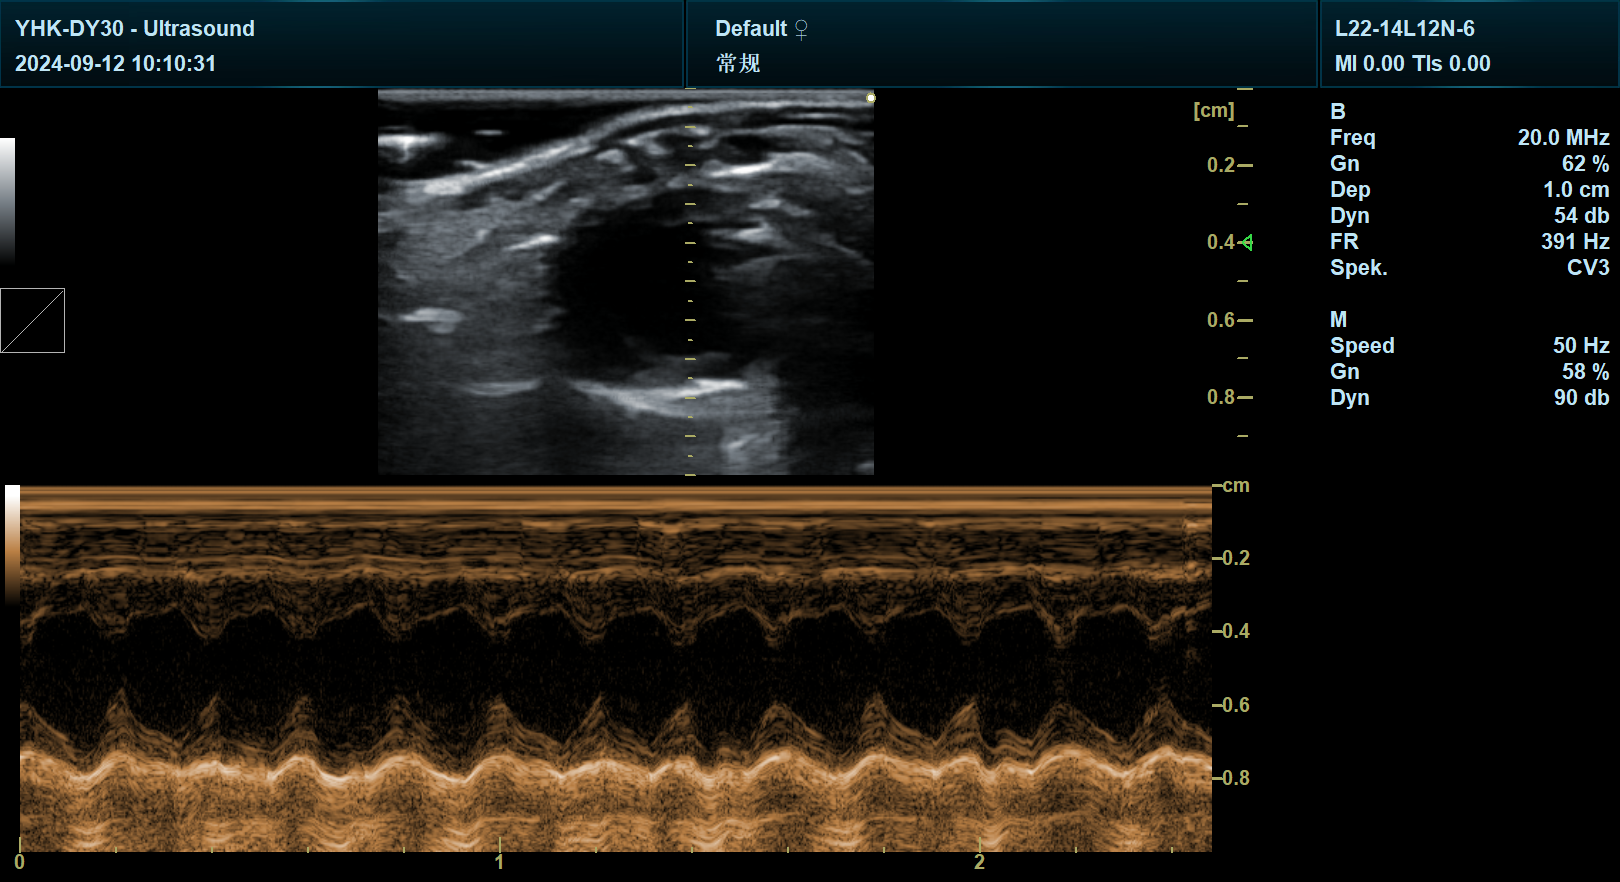

宜慧康YHK-DY30专业版系列搭载18MHz超高频线阵探头,配合12-25MHz可调频率范围,可实现心脏、血管、肿瘤等微小结构的毫米级成像。例如,在心血管疾病模型研究中,该设备能清晰显示小鼠心肌纤维走向、瓣膜开闭幅度及冠状动脉分支,为心肌梗死、心力衰竭等机制研究提供可视化依据。上海交通大学医学院实验动物中心数据显示,使用宜慧康设备后,小鼠心脏模型构建成功率提升40%,数据采集效率提高65%。

设备集成B超、彩色多普勒、频谱多普勒、弹性成像四大核心模块,支持从解剖结构观察到血流动力学分析的全链条研究。在肿瘤转移模型中,科研人员可通过弹性成像量化肿瘤硬度变化,结合血流频谱分析评估抗血管生成药物疗效。北京大学生命科学学院利用该技术,成功揭示乳腺癌转移的力学机制,相关成果发表于《Nature Communications》。